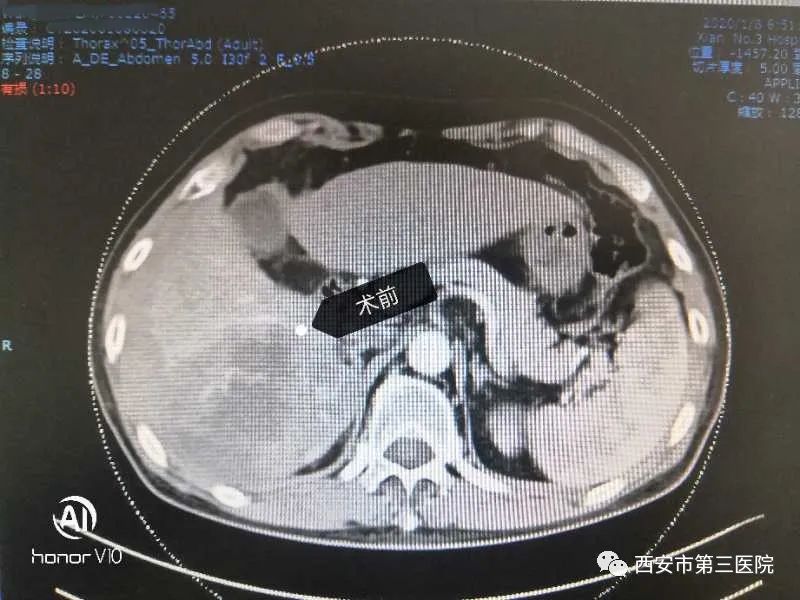

近日,西北大学附属医院•西安市第三医院消化内科为一名肝癌中晚期患者实施D-TACE治疗,术后巨块型肿瘤明显缩小,肿瘤标志物甲胎蛋白从高出正常值数百倍将至基本正常水平;患者原有的腹痛、腹胀症状基本消失,回到正常工作生活。